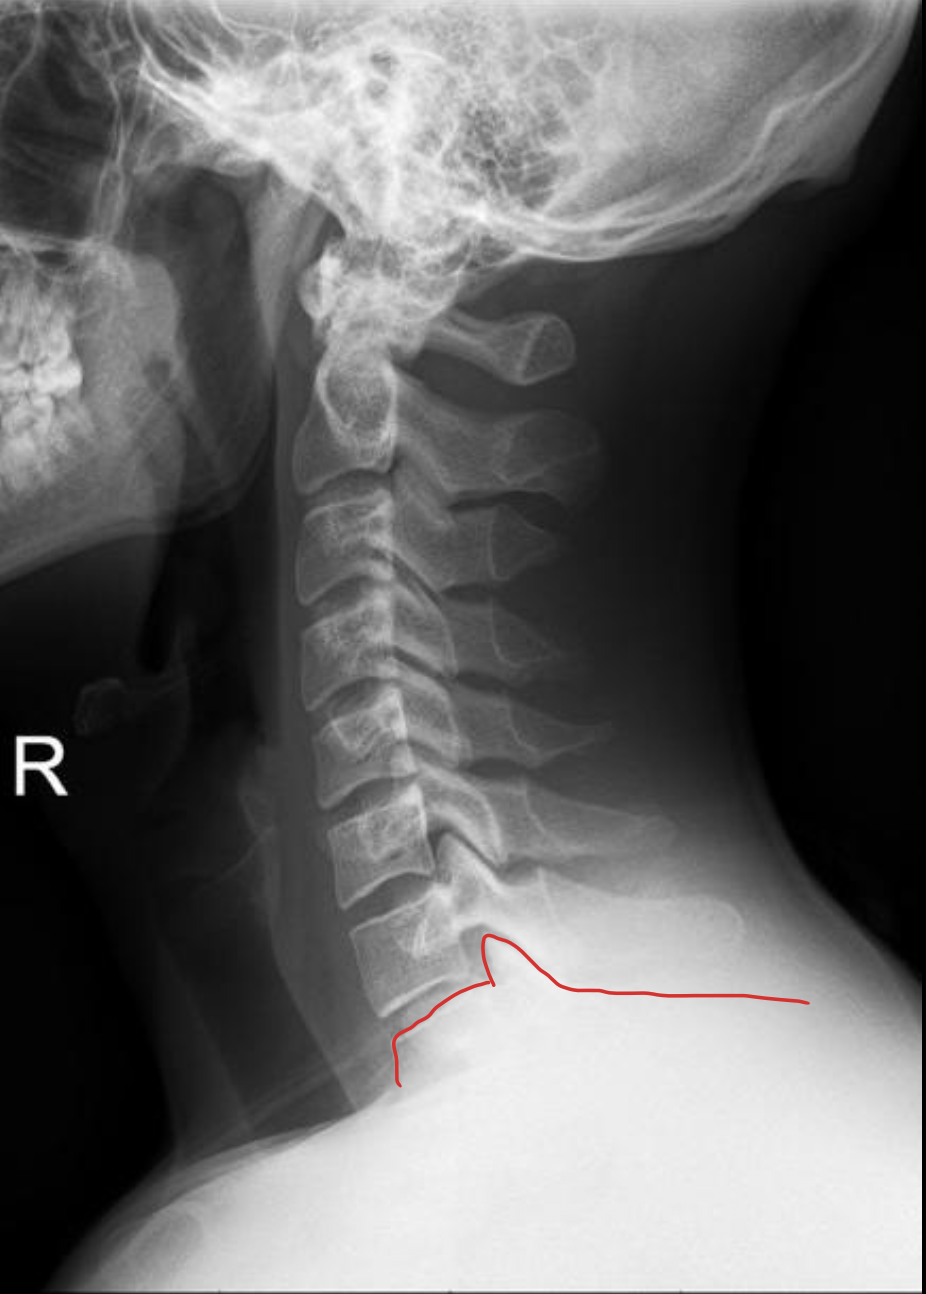

T1

1ST Rib